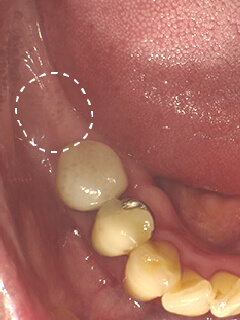

インプラントの治療例

インプラントにかぶせ物を装着後